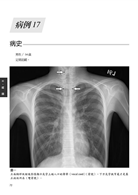

病例17 氣管狹窄(Tracheal stenosis)∕氣管插管後之後遺症 72